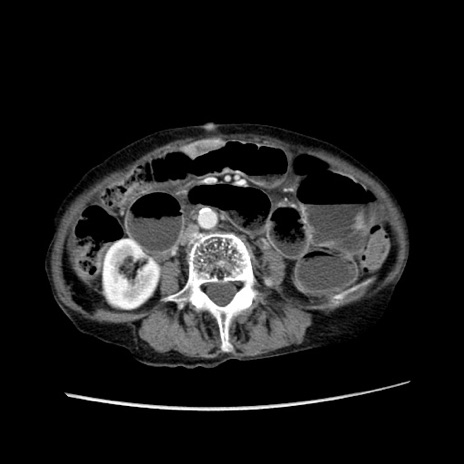

症例25(横断像)

【症例】80歳代女性

【主訴】胸のつかえ感

【現病歴】約9時間前に食後から胸のつかえた感じあり、嘔吐あり、来院。

【既往歴】胃癌(全摘)、胆摘、虫垂炎

【身体所見】心窩部に圧痛あり、反跳痛なし。

【データ】WBC 5700、CRP 0.05